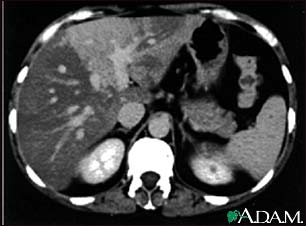

A CT scan of the upper abdomen showing disproportional steatosis (fattening) of the liver.